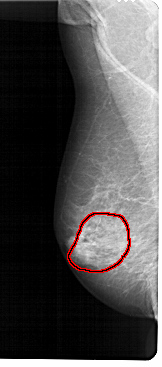

A_1302_1.RIGHT_MLO

FILE: A_1302_1.RIGHT_MLO.OVERLAY

TOTAL_ABNORMALITIES 1

ABNORMALITY 1

LESION_TYPE CALCIFICATION TYPE PUNCTATE-AMORPHOUS DISTRIBUTION REGIONAL

ASSESSMENT 4

SUBTLETY 3

PATHOLOGY BENIGN

TOTAL_OUTLINES 1

BOUNDARY